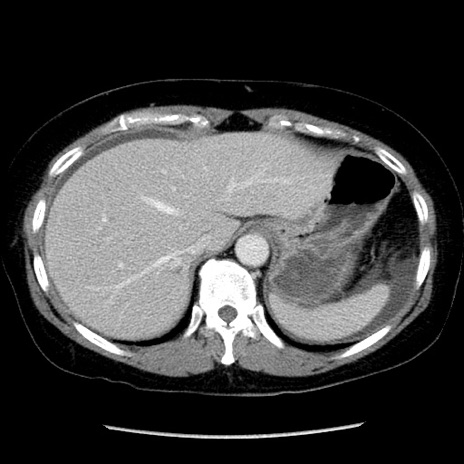

症例6(横断像)

【症例】50歳代女性

【主訴】下腹部痛

【現病歴】本日朝より下痢2回あり。 昼食を食べた後、嘔吐3回、下腹部痛認め、症状軽快せず、当院救急搬送。

【既往歴】卵巣癌術後(8年前に当院で卵巣摘出)

【身体所見】 意識清明、腹部:平坦、腸蠕動音→、やや硬、下腹部自発痛・圧痛あり、反跳痛あり、筋性防御なし。

【データ】WBC 16000、CRP 0.01